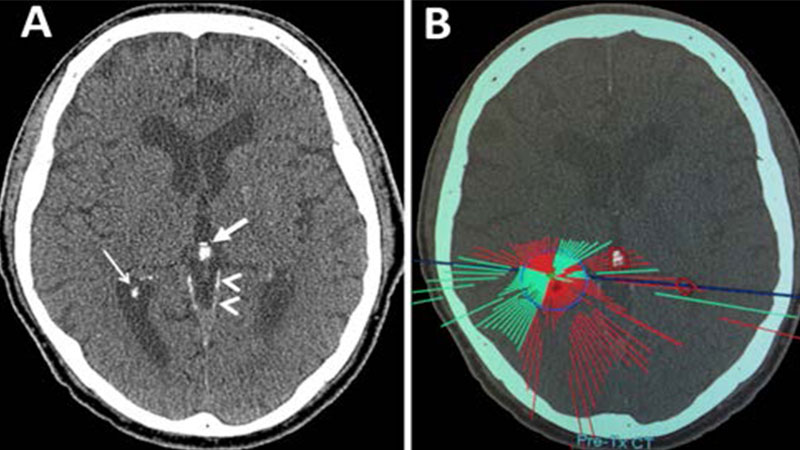

MRgFUS treatment plan of a study patient accounting for intracranial calcifications. A: Axial noncontrast image showing dural (arrowheads), choroid plexus (narrow arrow), and pineal (wide arrow) calcifications in the region of the treatment target. B: Pretreatment plan demonstrating ultrasound elements reaching target (green) and being blocked (red) due to intracranial calcifications. Patient had inadequate element availability secondary to intracranial calcifications.